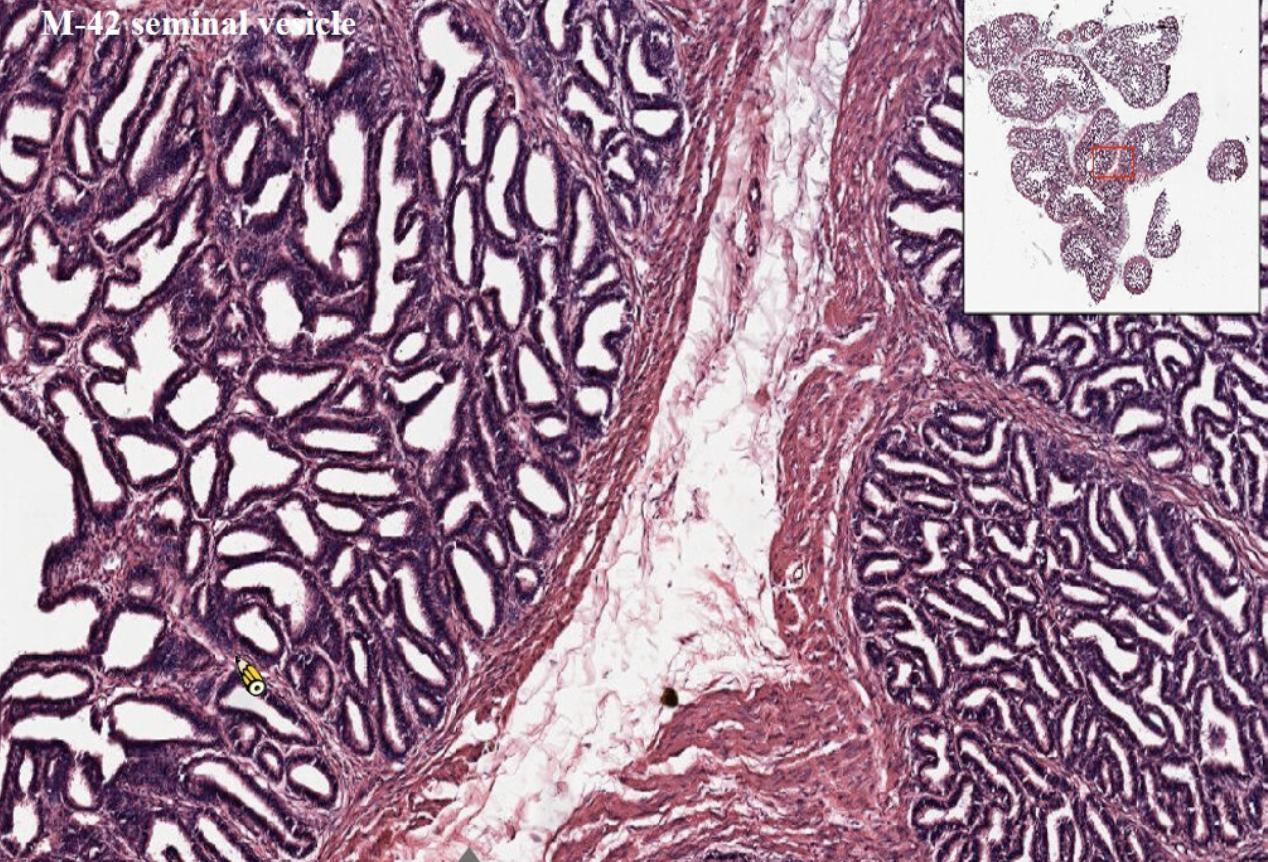

- 約250 個小葉

- TA: Dense irregular

- Tunica (lamina) propria

- Wave of the seminiferous tubule

Prostate Gland

- Peripheral zone

- Transitional zone

- Prostatic concretions (CA)

- 年輪狀,填在線體裡面